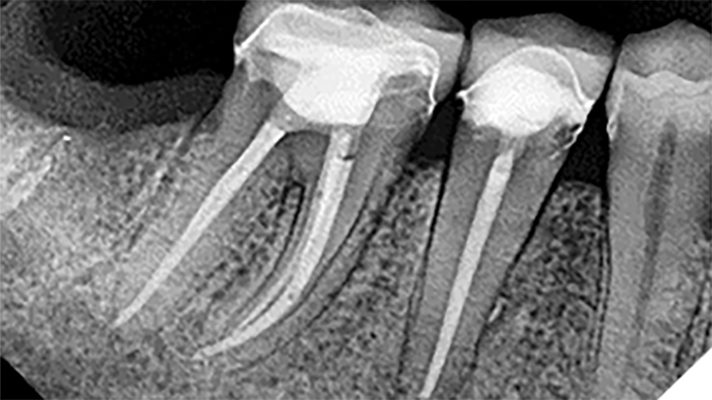

Root canal shaping in the age of minimally invasive endodontics (MIE)

”You cannot clean a root canal with a larger file.” — LSB We are entering a new golden age of endodontics where instrumentation with root canal files is safer, easier, and more efficient. In 1980, when the senior author matriculated from his endo residency at Temple University, the most difficult art form in clinical endodontics was … Read more